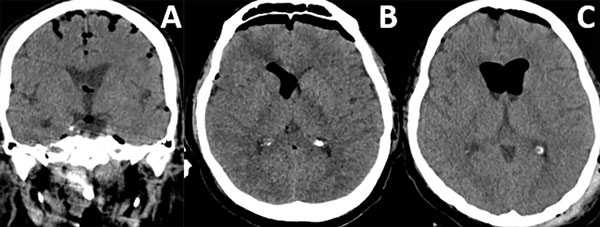

Patrones y grados de NE: NE subdural (Figura 1), se clasificó en 3 grados: leve (menor al espesor óseo), moderado (entre una vez y dos veces el espesor óseo) y severo (dos o más veces el espesor óseo). NE subaracnoideo (Figura 2), se clasificó en 3 grados: leve (confinado a cisternas basales), moderado (cisternas supratentoriales predominio unilateral), severo (generalizado). NE ventricular (Figura 3), se clasificó en: leve (en IV y/o III ventrículo), moderado (alcanzó VL), severo (alcanzó y dilató los VL).

Figura 1. Neumoencéfalo subdural. A) Leve. B) Moderado. C) Severo.